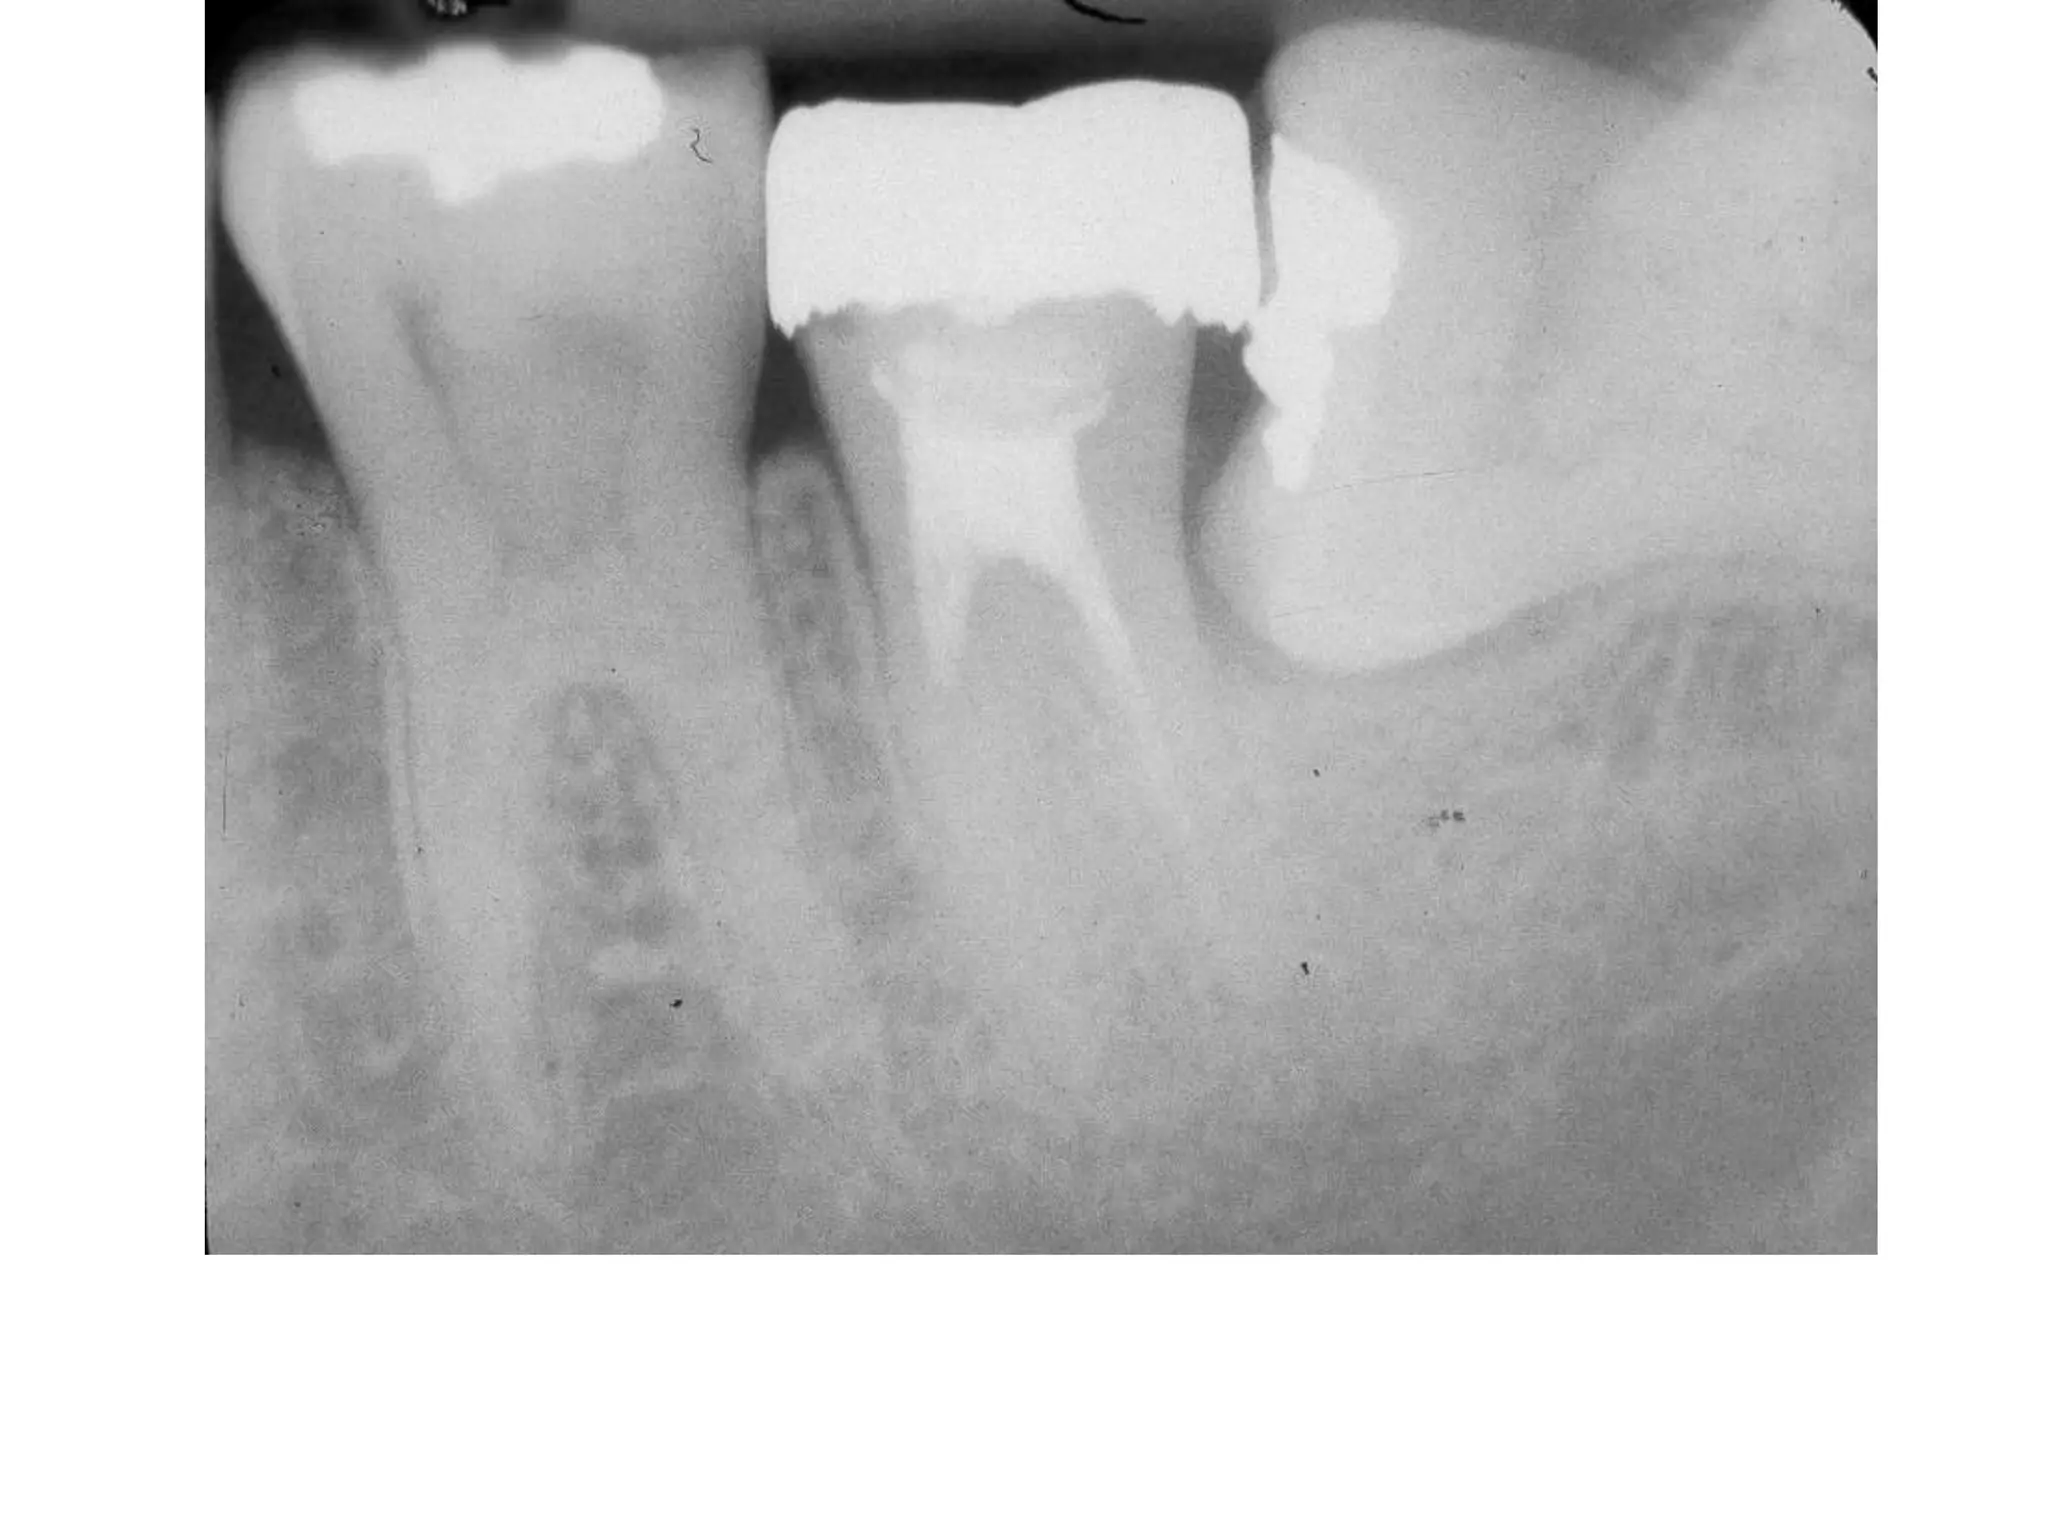

Severe Adult Periodontitis

Tooth mobility

Extensive horizontal bone

loss or vertical osseous

defects

Furcation involvement